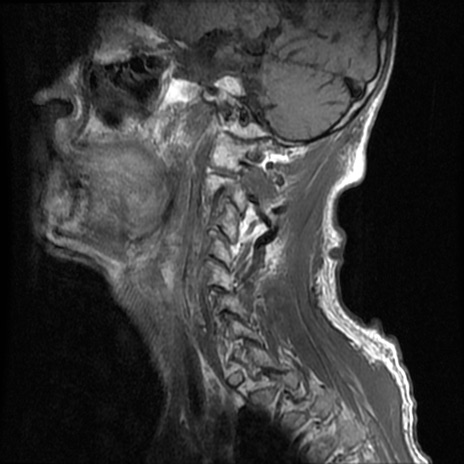

症例46 頚椎MRI T1WI(矢状断像)

頚椎MRI

T2WI(矢状断像)